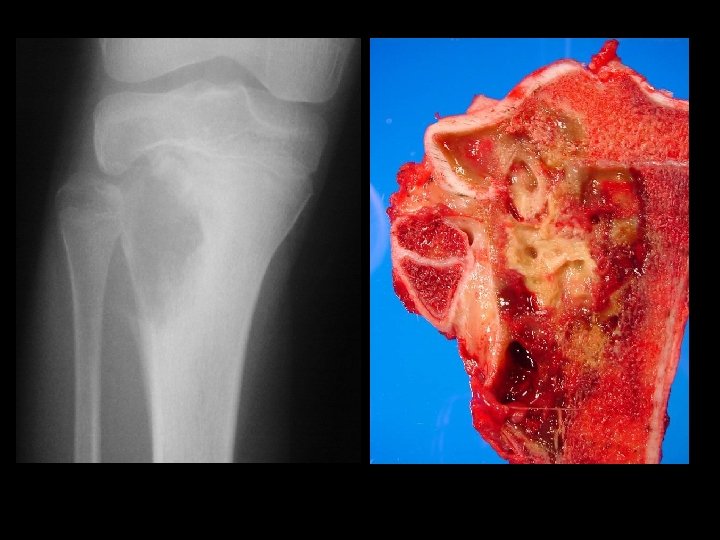

Giant cell tumour • • Uncertain origin Occurs in mature bone Area of old epiphysis Distal femur, proximal tibia, proximal humerus, distal radius.

Example 4*, 35 y/o F, GCT